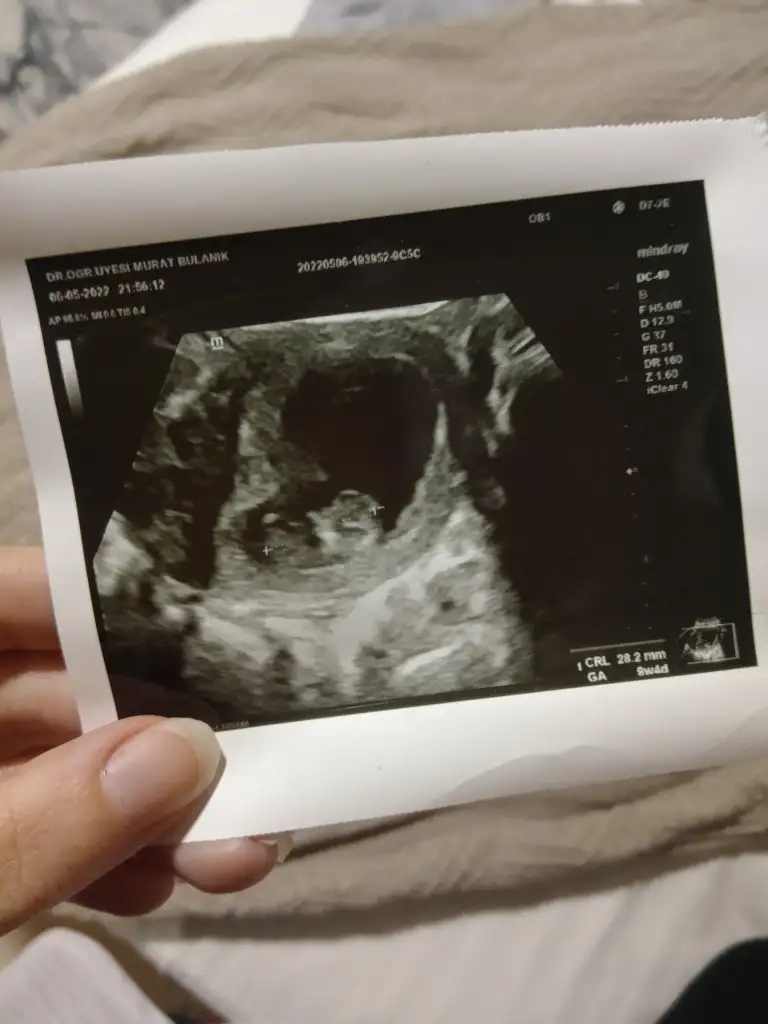

Merhaba tam 8 haftalık karından bana da yorum yaparmısınız ?